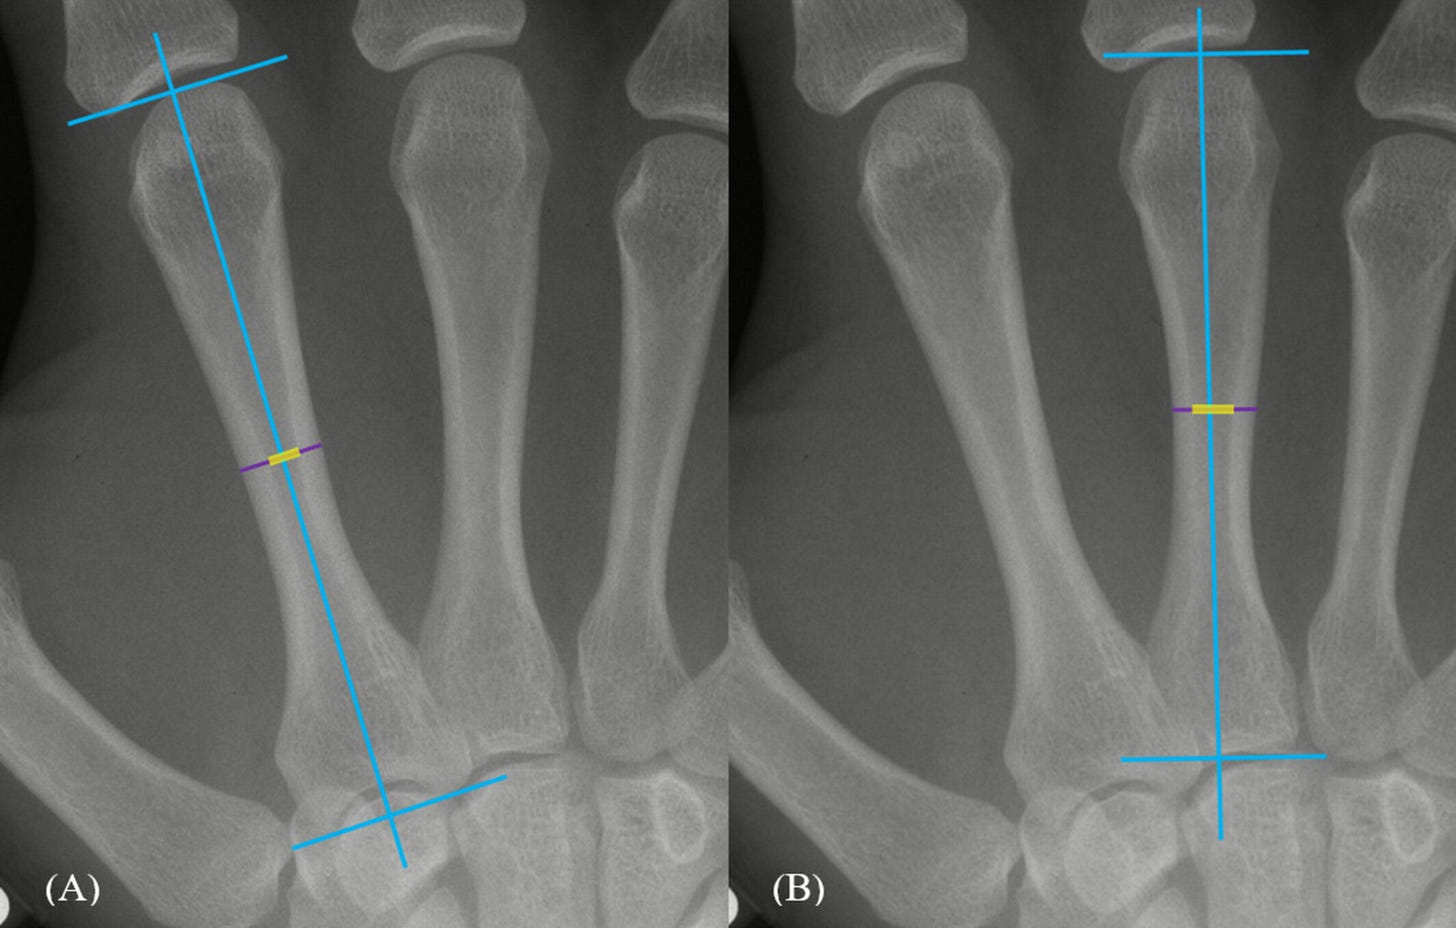

A new longitudinal study1 of adolescents and young adults shows that even after the hormonal storms of puberty have passed, the human skeleton continues to quietly remodel itself. The evidence comes not from dramatic changes in stature or limb length, but from the slow thickening of cortical bone in the metacarpals, the slender bones that form the framework of the hand. These changes extend well into the late teenage years and beyond, challenging assumptions that have shaped biological anthropology, forensic science, and interpretations of the fossil record.